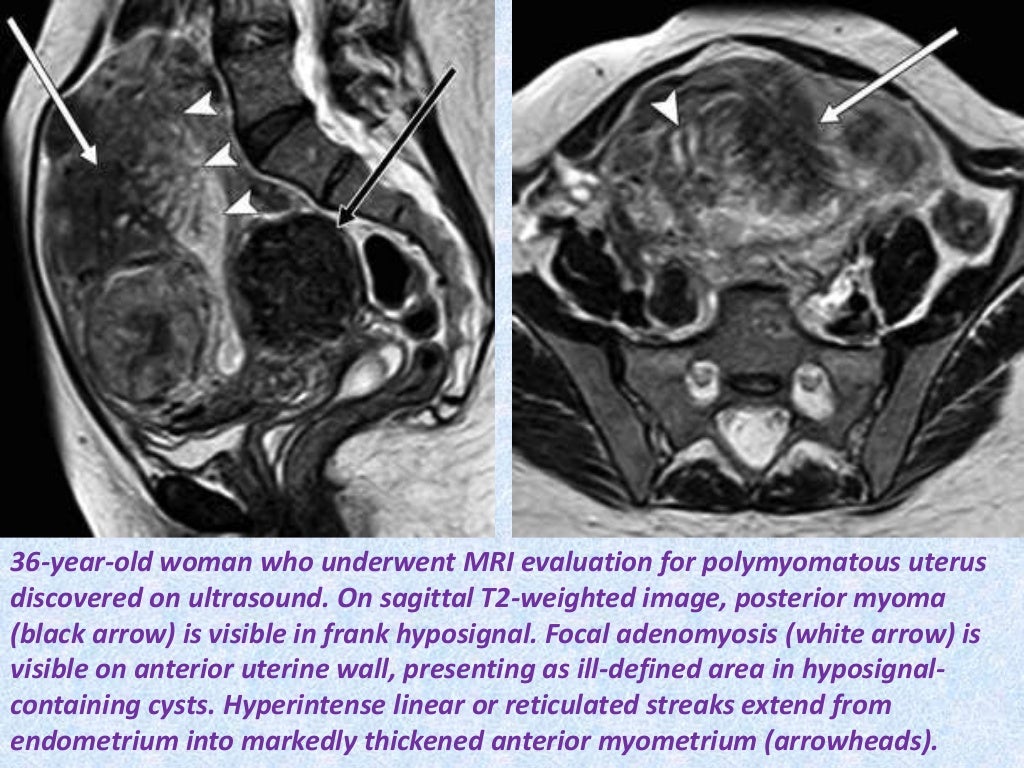

MRI findings in deep infiltrating endometriosis A pictorial essay Does Endometriosis Show Up In Ct Scan Density of small diameter sensory nerve fibres in endometrium: bokor a, kyama cm, vercruysse l, et al. Knowing the locations of possible endometriosis can aid your surgeon in planning your surgery. based on clinical suspicion or findings at routine transvaginal pelvic us or other prior imaging, dedicated imaging for. to find out if you have endometriosis, your. Does Endometriosis Show Up In Ct Scan.

From pubs.rsna.org

MR Imaging in Deep Pelvic Endometriosis A Pictorial Essay RadioGraphics Does Endometriosis Show Up In Ct Scan the article presents 10 observations, based on the authors’ experience, to aid radiologists in the identification and characterization of the various manifestations of endometriosis that may be encountered at mr imaging in the female pelvis. based on clinical suspicion or findings at routine transvaginal pelvic us or other prior imaging, dedicated imaging for. bokor a, kyama cm,. Does Endometriosis Show Up In Ct Scan.